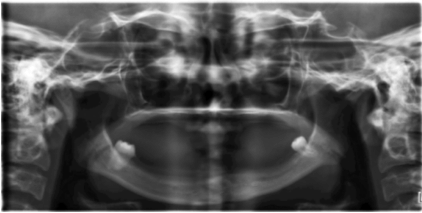

Case 2: A 26-year-old woman came to our department on the request of her brother (case 1) for examination for this study. On general examination, it was found that, she had normal physical and mental development. Physical examination revealed symmetrical, but not a well formed keratotic plaques on the skin of the palms and soles. The extension of these plaques to the dorsal surface of the finger joints and also over the dorsal surfaces of the feet was mild and not as marked as in case 1 (Figure 4). She gave a history that the keratotic plaques was marked and well demarcated, similar to her brother but later, the keratotic plaques were peeled from the skin surface after applying a medicine given to her by her dermatologist. On intra-oral examination, it was found that she was wearing a complete denture set for ten years. All her permanent tooth were lost at the age of 15, except her lower third molar, which persisted with marked inflammation around the tooth (Figure 5). The edentulous area other than the lower third molar was normal with out any inflammation. The dental panoramic radiograph showed severe bone loss in relation to the lower third molar and the resorption of the ridge was severe (Figure 6). The lateral view of the skull radiograph showed no evidence of intracranial calcification.

Figure 6: The dental radiograph showing severe alveolar bone loss giving the teeth "floating in air" appearance in the female patient (case 2).